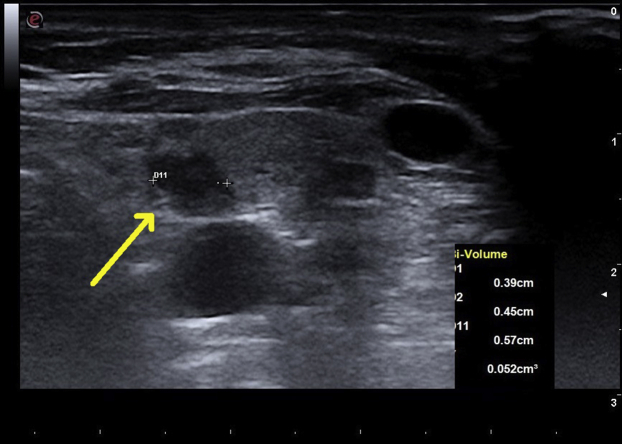

She was examined in clinic 10 days after RFA; she had no swallowing difficulty, breathing difficulty, cough, or hoarseness of voice. Both the calcium (10.1 mg/dL) and iPTH levels (85 pg/mL) were normalized. The ablated parathyroid adenoma was smaller, with ultrasonography showing decreased Doppler blood flow. However, a polar artery was still present. She felt well during her 6-month follow-up. Her laboratory study results indicated a serum calcium level of 10.2 mg/dL, iPTH level of 75 pg/mL, 25-hydroxy vitamin D level of 68 ng/mL, thyroid-stimulating hormone level of 1.63 mIU/L (normal range: 0.46-4.88 mIU/L), and free thyroxine level of 0.93 ng/dL (normal range: 0.75-1.5 ng/dL). A repeat ultrasound of her neck at this visit (Fig. 3) showed that the previously ablated parathyroid adenoma now measured 0.57 cm × 0.45 cm × 0.39 cm (volume: 0.05 cm3). Doppler blood flow observed using ultrasonography showed that the adenoma was now avascular, with the polar artery no longer visible. She was examined again 12 months after RFA and was noted to have a serum calcium level of 9.8 mg/dL and an iPTH level of 84 pg/mL. Ultrasonography showed that her adenoma now measured 0.54 cm × 0.24 cm × 0.47 cm (volume: 0.03 cm3) (Fig. 4). This represented a volume reduction of 80.7% compared with the volume seen in the initial neck ultrasonography, allowing for intraobserver variability of measurement, which was a significant decrease.

Fig. 3.

Neck ultrasonogram in sagittal view 6 months after RFA of the left inferior parathyroid adenoma. The yellow arrow indicates a hypoechoic nodule representing an adenoma now measuring 0.57 cm in length, 0.39 cm in depth, and 0.45 cm in width, with a calculated volume of 0.052 cm3. RFA = radiofrequency ablation.